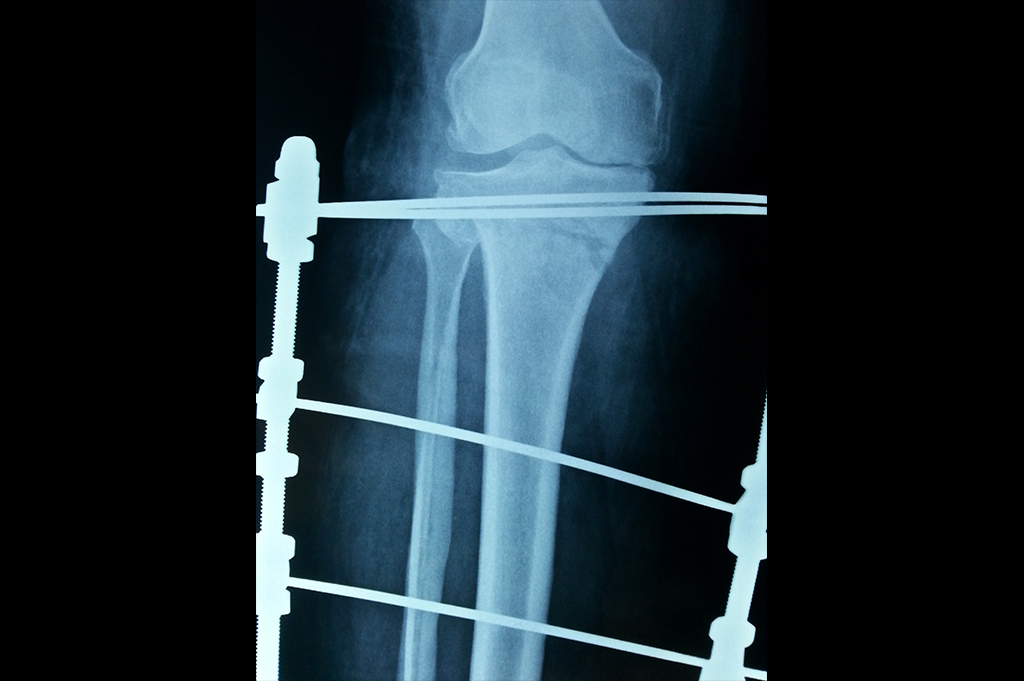

Proximal Tibia